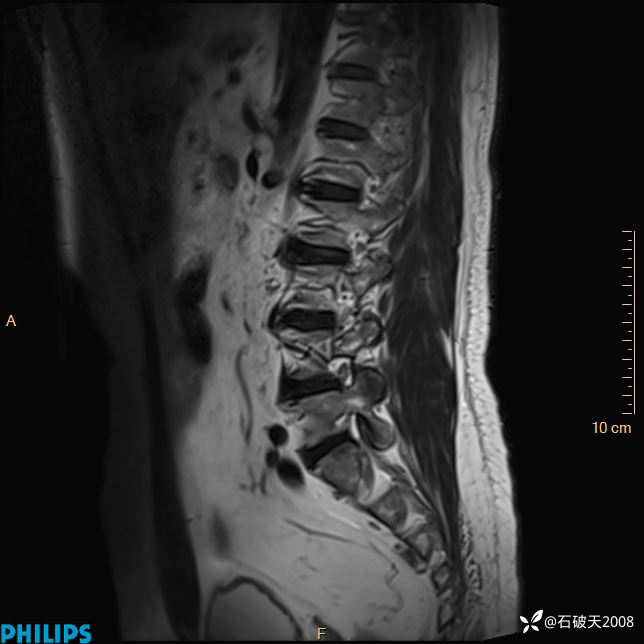

2023年3月份MRI影像

T1矢状位